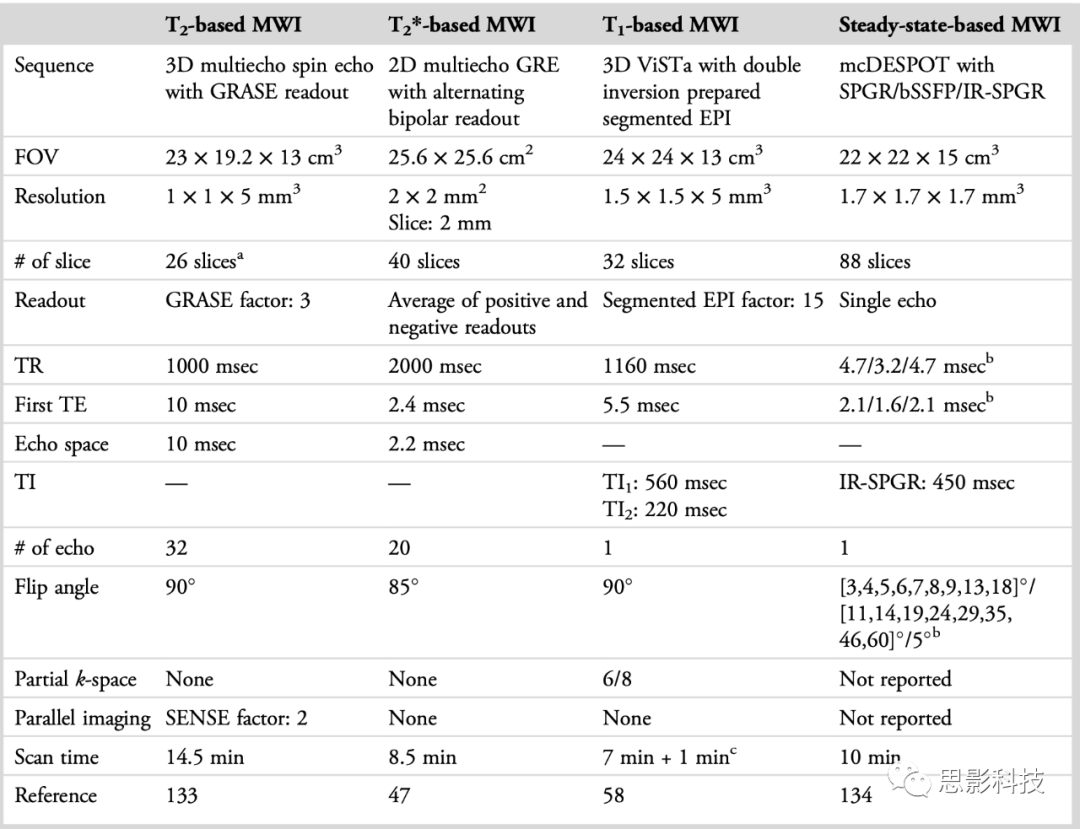

表2:四种髓鞘水成像方法的典型扫描协议摘要

[*] 切片过采样被忽略。 [†] 值按照SPGR、bSSFP和IR-SPGR的顺序列出。 [†] 参考扫描时间。参考扫描是计算表观MWF所必需的。 在表2中,总结了近期研究中四种方法的扫描参数。